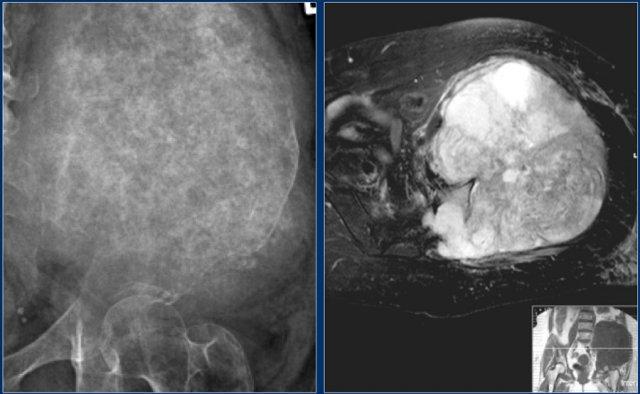

Here a chondrosarcoma of the left iliac bone.

Do kích thước lớn với sự lan rộng vào mô mềm trên phim X-quang thường và hình ảnh MRI chuỗi xung T2 trục, u sụn ác tính độ cao đã được nghi ngờ.

Biopsy showed grade 2 chondroarcoma.